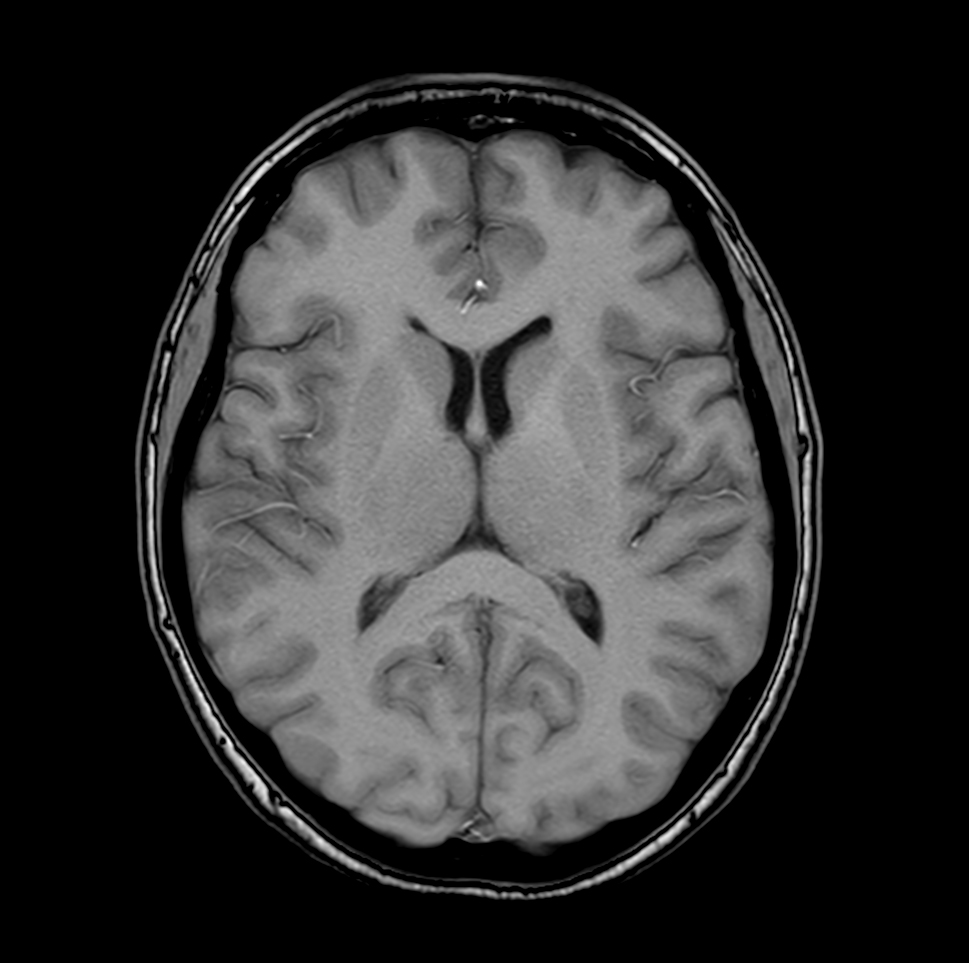

Axial T1w SE

Axial T1w FFE